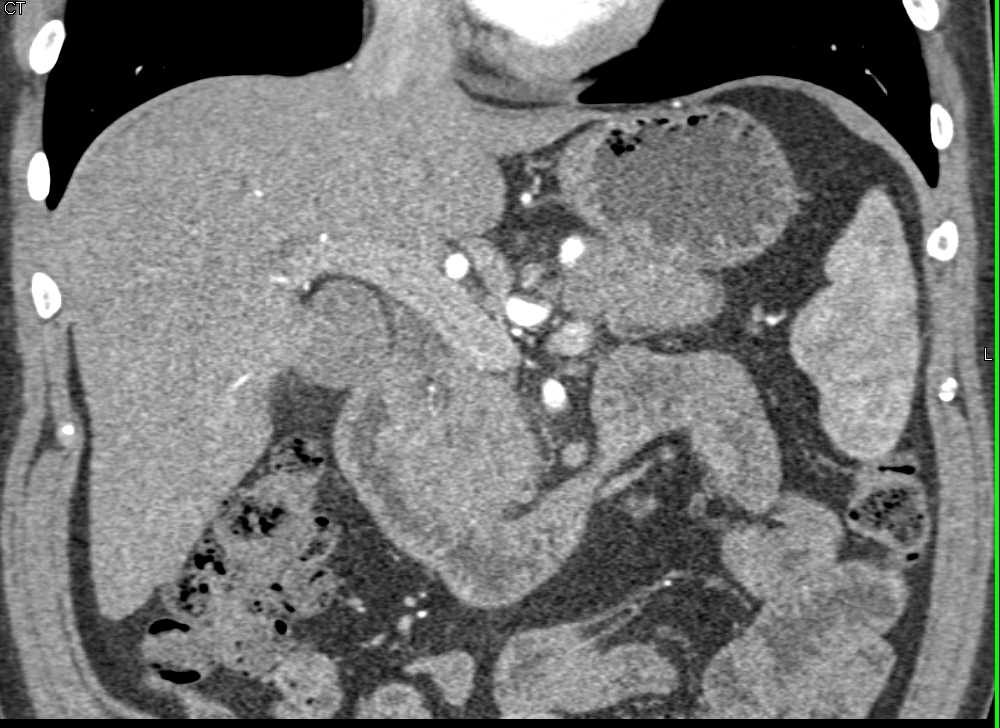

Duodenal Adenocarcinoma Simulates a Pancreatic Adenocarcinoma